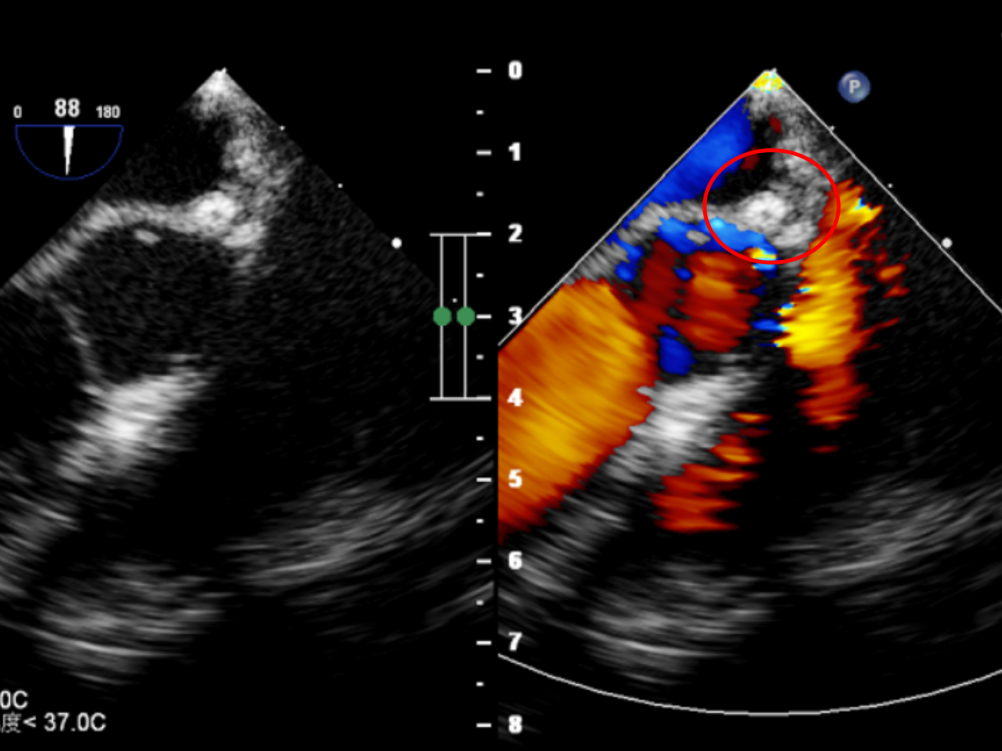

术后超声检查

超声下可见封堵器形态位置正确,未见明显血流通过,封堵器盘面贴合,位置固定